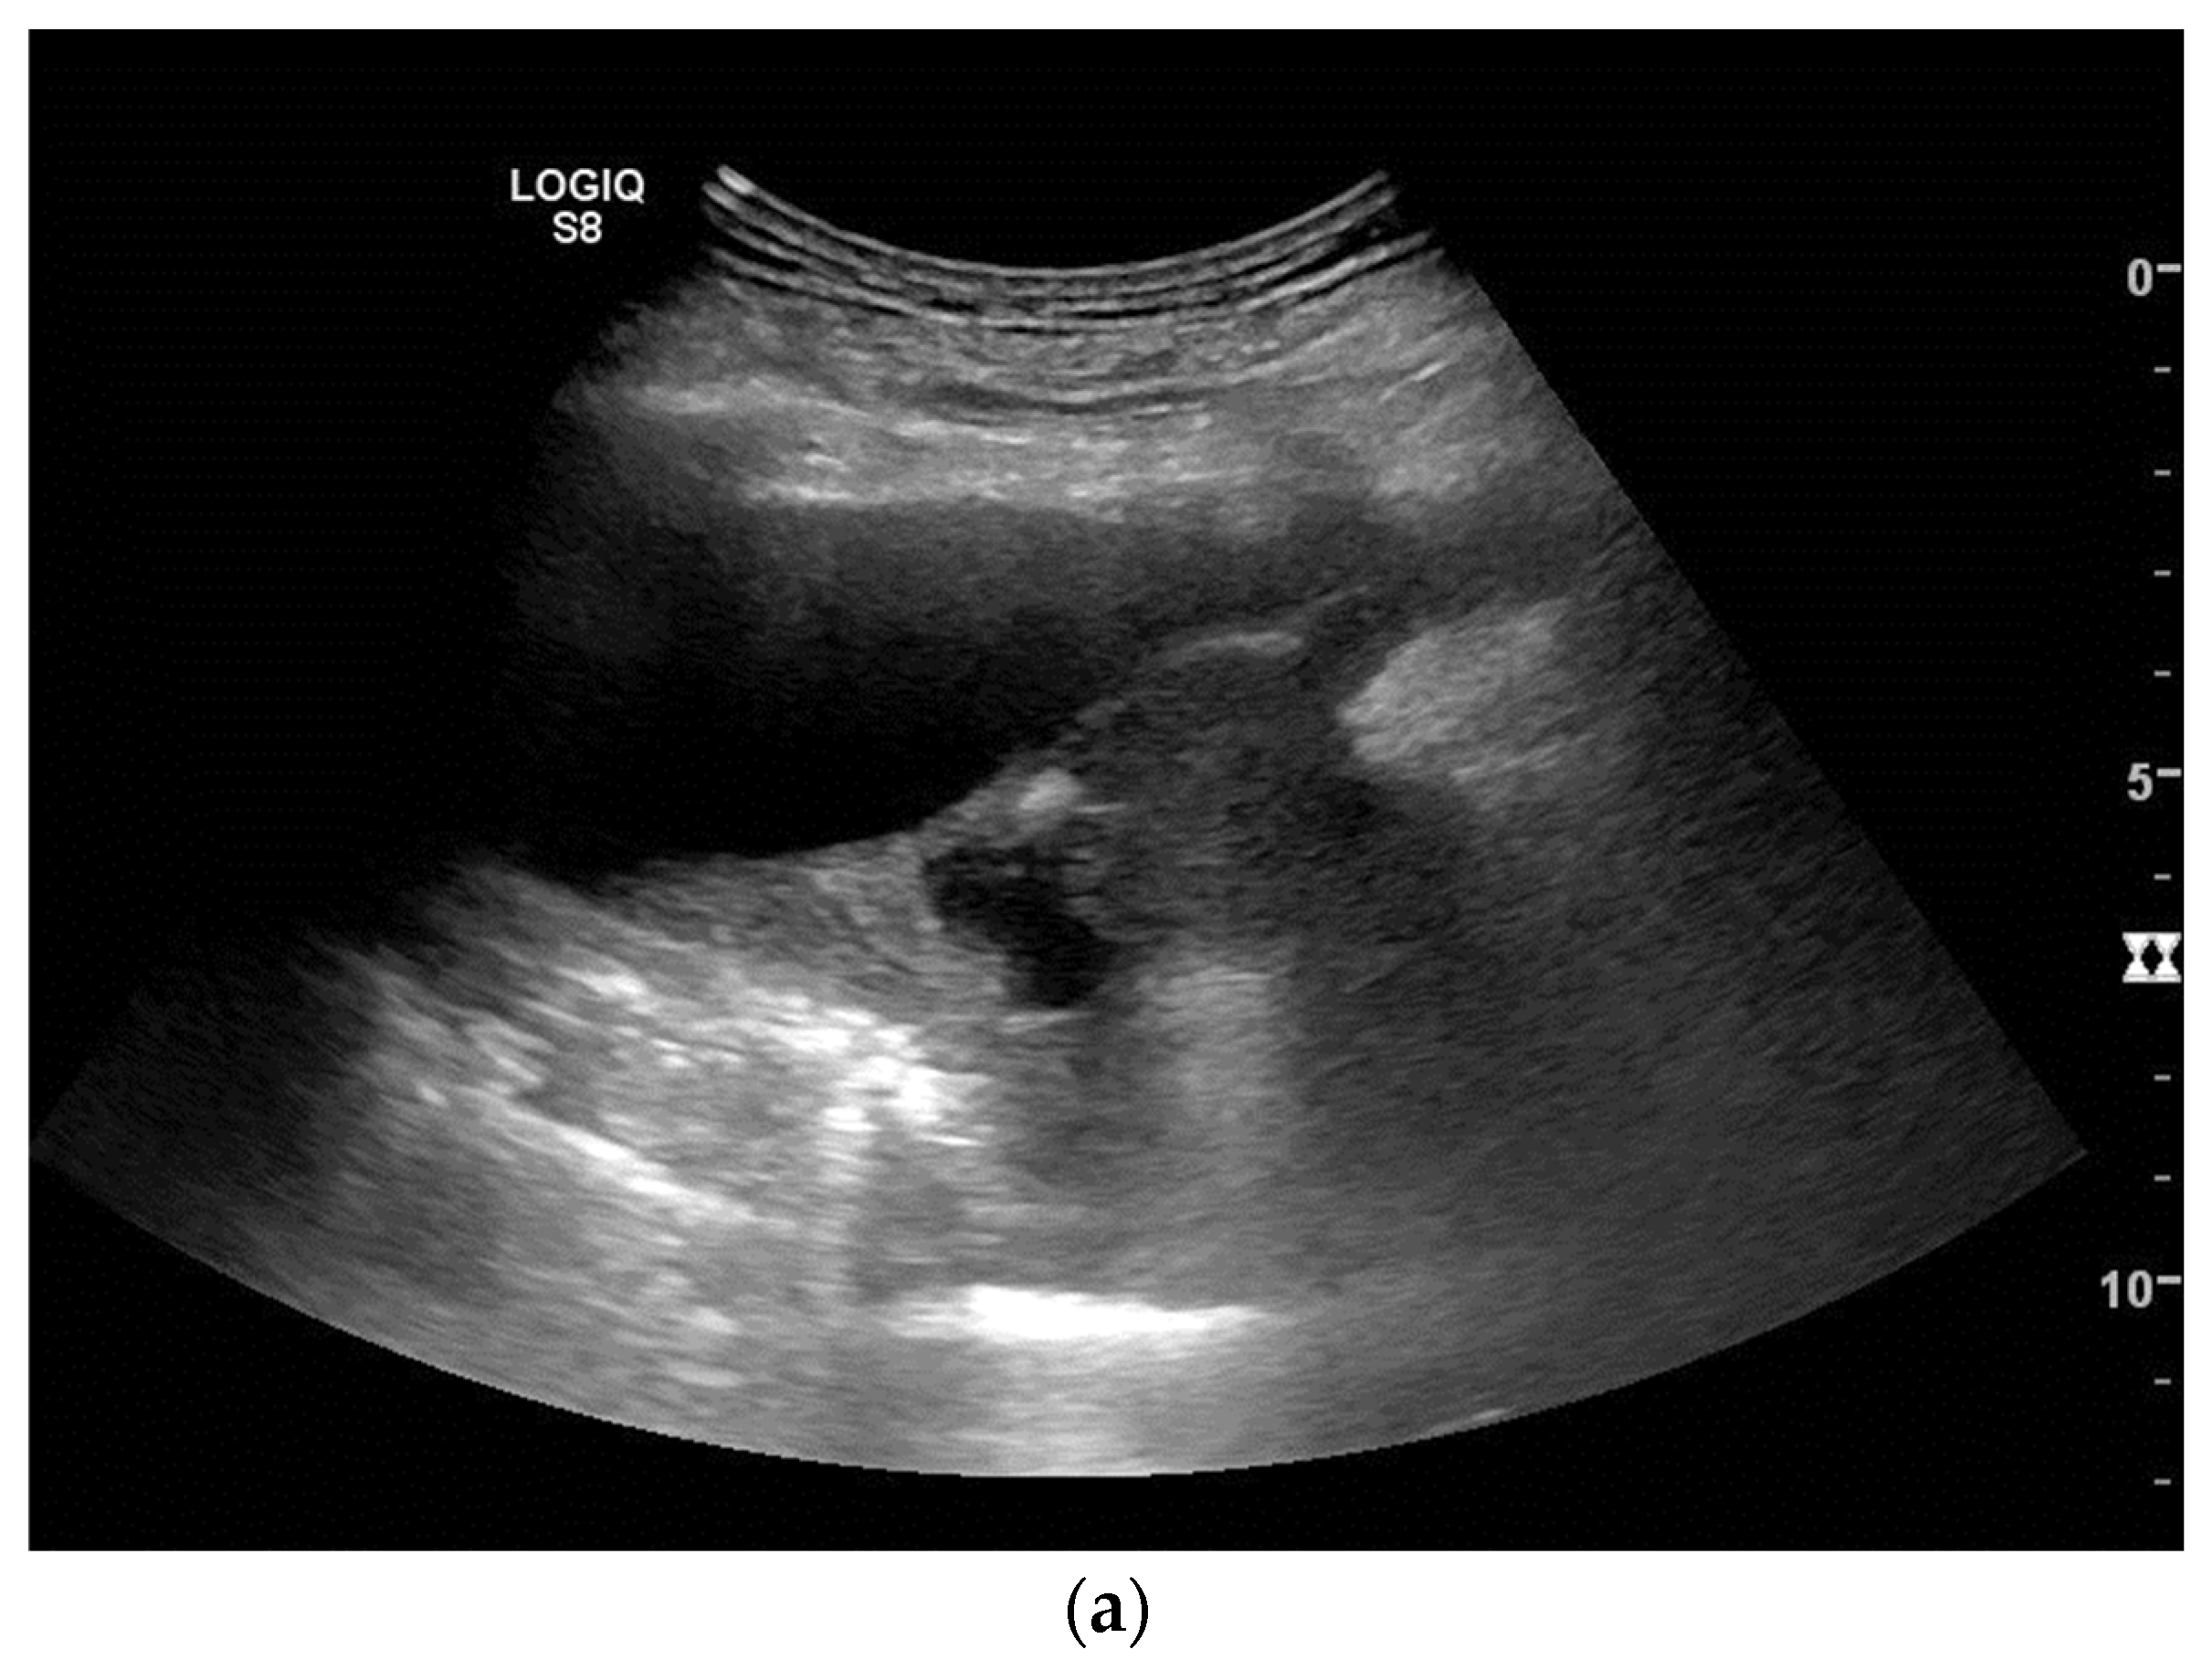

2. Primary Pulmonary Sarcomas